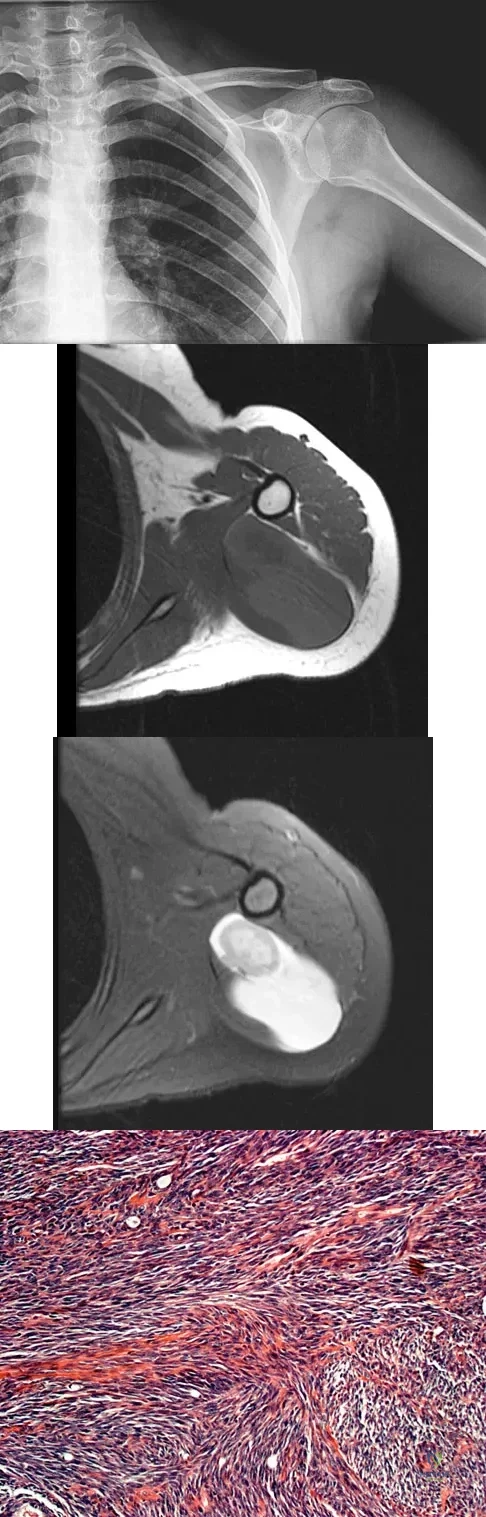

A 16-year-old girl has had painless swelling in her posterior left arm for the past 4 months. A radiograph, MRI scans, and an incisional biopsy specimen are shown in Figures 43a through 43d. What is the cytogenetic translocation most commonly associated with this tumor?

Explanation